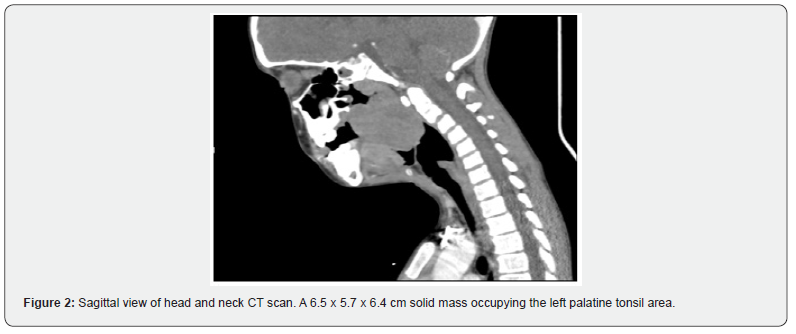

He was drooling and compensating with smaller breaths and faster respiratory rate. Preoperative physical examination revealed a large vascular-rich mass protruding into the oral cavity. The oropharynx was difficult to visualize (Figure 1). The neck CT shows a 6.5 x 5.7 x 6.4 cm solid mass occupying the left palatine tonsil area (Figure 2).